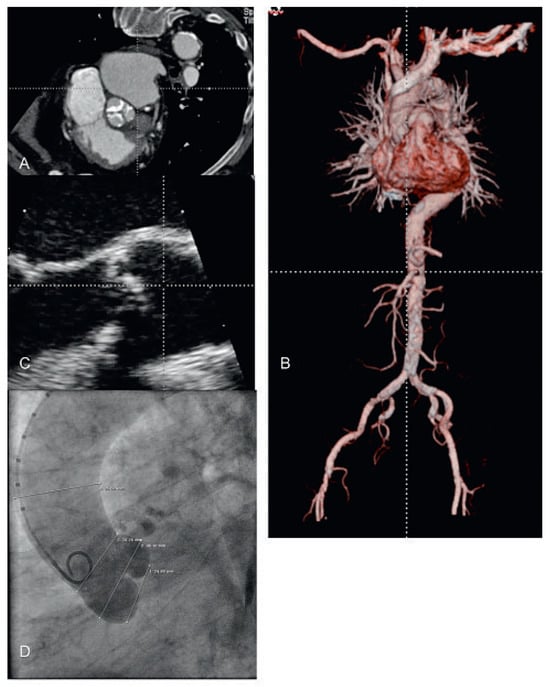

Abbildung 7. Vorabklärung vor Transkatheter-Aortenklappen-Implantation (TAVI). (A) Angio-CT; Aufsicht auf die verkalkte Aortenklappe. (B) Angio-CT mit dreidimensionaler Rekonstruktion des peripheren Zuganges. (C) Transösophageale Echokardiographie zur Ausmessung des Aortenannulus. (D) Aortograpahie mit Ausmessung des Annulus, des Sinus und des sinotubulären Überganges.